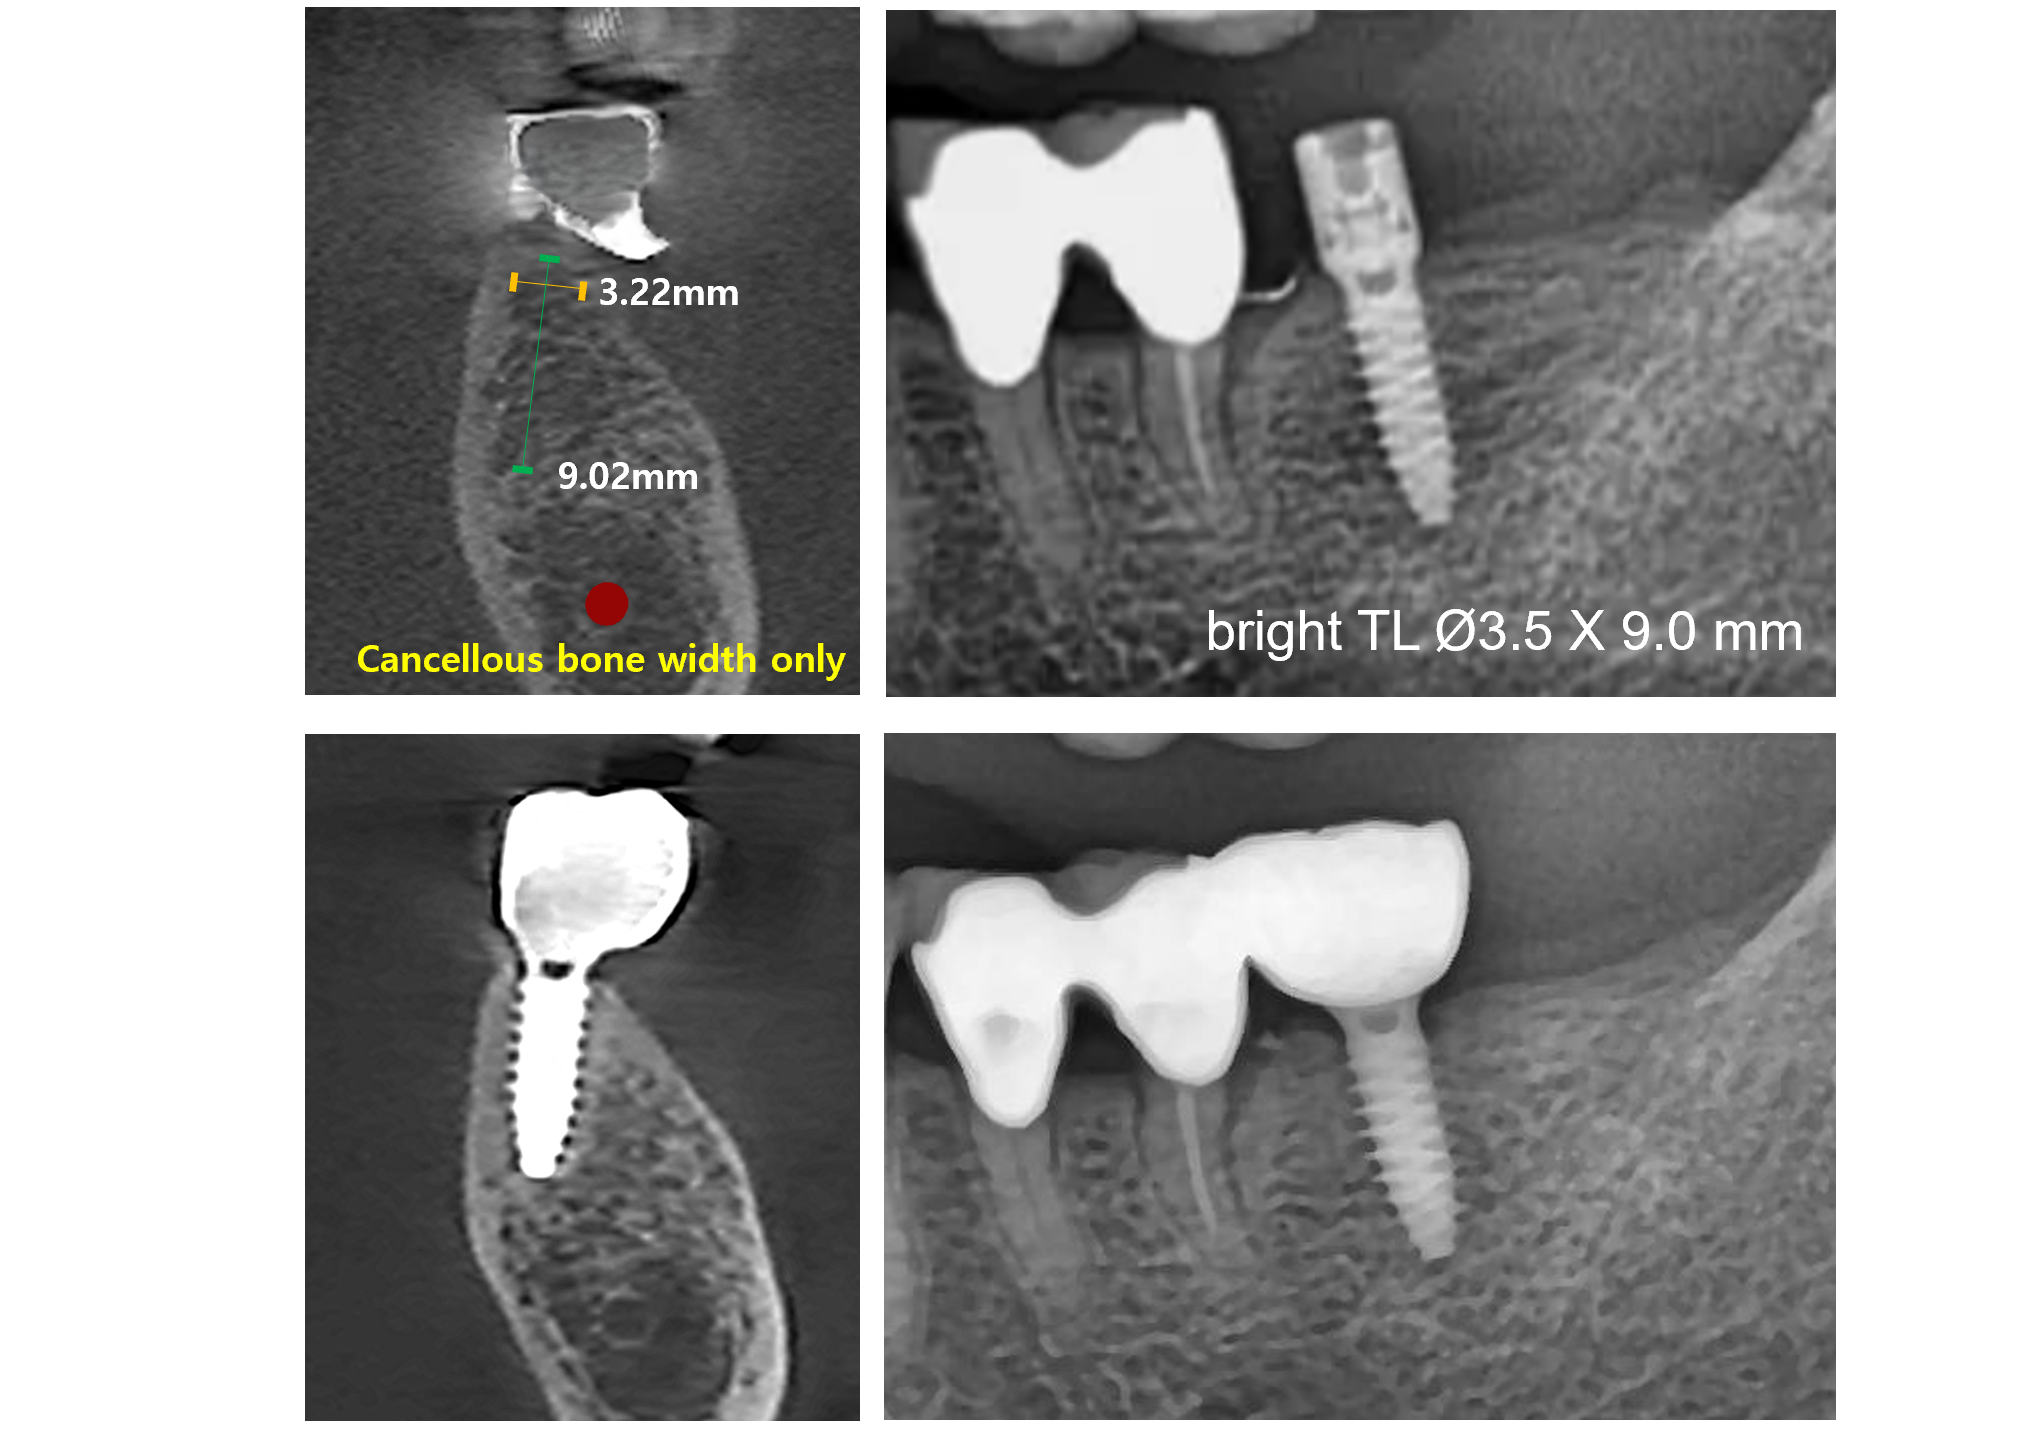

Narrow but Strong

With a reinforced internal structure, the narrow-diameter bright implants can be used for challenging clinical situations with narrow ridges.

Diameters as narrow as 3.5mm provide reliable solutions even in posterior regions.